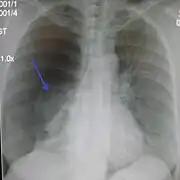

Chest X-ray

A plain chest radiograph, ideally with the X-ray beams being projected from the back (posteroanterior, or "PA"), and during maximal inspiration (holding one's breath), is the most appropriate first investigation.[32] It is not believed that routinely taking images during expiration would confer any benefit.[33] Still, they may be useful in the detection of a pneumothorax when clinical suspicion is high but yet an inspiratory radiograph appears normal.[34] Also, if the PA X-ray does not show a pneumothorax but there is a strong suspicion of one, lateral X-rays (with beams projecting from the side) may be performed, but this is not routine practice.[15][19]

Chest X-ray showing a pneumothorax on the right (left in the image), where the absence of lung markings indicates that there is free air inside the chest

Chest X-ray showing the features of pneumothorax on the left side of the person (right in image)

It is not unusual for the mediastinum (the structure between the lungs that contains the heart, great blood vessels, and large airways) to be shifted away from the affected lung due to the pressure differences. This is not equivalent to a tension pneumothorax, which is determined mainly by the constellation of symptoms, hypoxia, and shock.[13]

The size of the pneumothorax (i.e. the volume of air in the pleural space) can be determined with a reasonable degree of accuracy by measuring the distance between the chest wall and the lung. This is relevant to treatment, as smaller pneumothoraces may be managed differently. An air rim of 2 cm means that the pneumothorax occupies about 50% of the hemithorax.[15] British professional guidelines have traditionally stated that the measurement should be performed at the level of the hilum (where blood vessels and airways enter the lung) with 2 cm as the cutoff,[15] while American guidelines state that the measurement should be done at the apex (top) of the lung with 3 cm differentiating between a "small" and a "large" pneumothorax.[35] The latter method may overestimate the size of a pneumothorax if it is located mainly at the apex, which is a common occurrence.[15] The various methods correlate poorly but are the best easily available ways of estimating pneumothorax size.[15][19] CT scanning (see below) can provide a more accurate determination of the size of the pneumothorax, but its routine use in this setting is not recommended.[35]

Not all pneumothoraces are uniform; some only form a pocket of air in a particular place in the chest.[15] Small amounts of fluid may be noted on the chest X-ray (hydropneumothorax); this may be blood (hemopneumothorax).[13] In some cases, the only significant abnormality may be the "deep sulcus sign", in which the normally small space between the chest wall and the diaphragm appears enlarged due to the abnormal presence of fluid.[16]